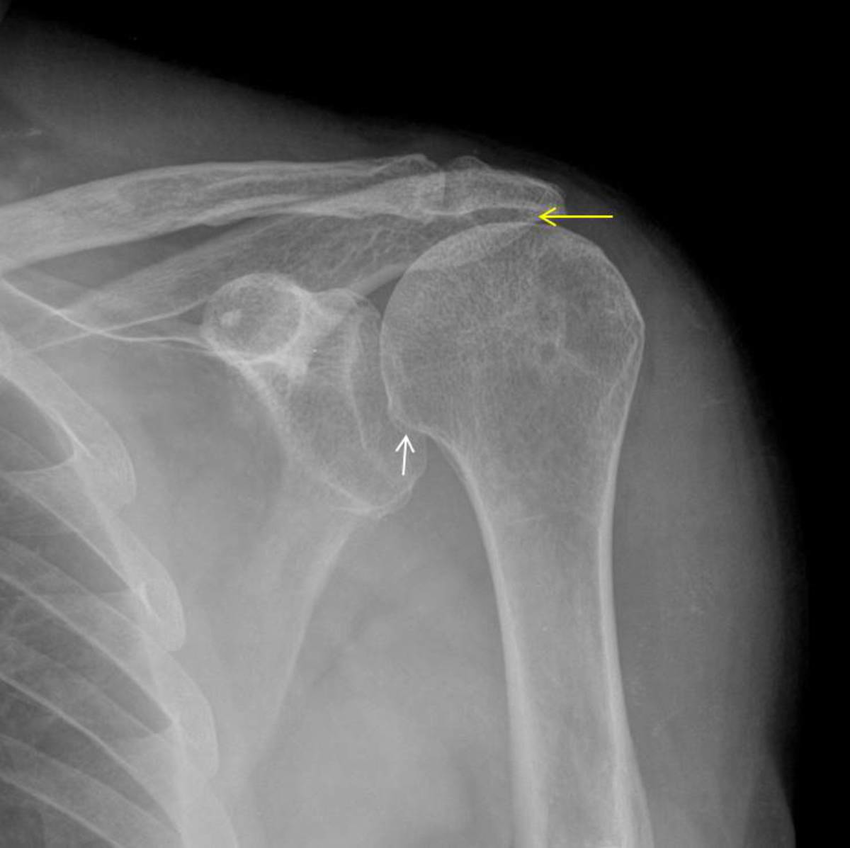

he deemed this joint the Acromiohumeral joint. It leads to a major insight

The shoulder is not a weight bearing joint, but it is weighted SUSPENDING

by hanging, the humerus is tractioned upward, and this suspension creates SPACE between the humerus and Acromion